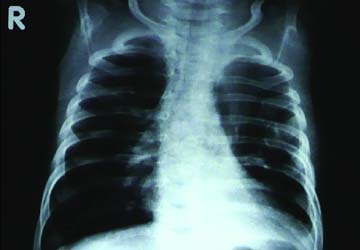

A chest radiograph was performed and is shown below. Radiographs: Diffuse subcutaneous emphysema and pneumomediastinum. Patchy basilar opacities In keeping with atelectasis and a probable small amount of left pleural fluid. Small biapical pneumothoraces